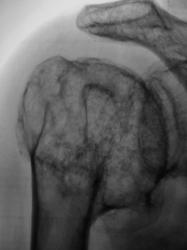

Какие будут мнения, уважаемые коллеги, по поводу изменений в головке плечевой кости. Жалоб пациент не предъявляет. Сустав при пальпации умеренно болезненный.

В структуре новообразования крапчатость, характерная для хрящевой ткани. Очень настораживает перерыв кортикального слоя локально, на участке, который наслаивается на основание большого бугорка

Несомненно есть патологический перелом хир. шейки плеча. Не представляю себе хондрому, которая занимает всю головку плеча вместе с бугорками и при этом за контуры почти не вылезает, да и структура всё же не беспорядочная. Подобные изменения как будто и в акромеоне и в теле лопатки. Нужна вторая проекция, а ещё лучше томограммы. Тут нечто доброкачественное.

Касательно темы... Валентин Львович попросил меня высказать мнение по этому снимку в форуме модераторов. Первое о чем я подумала - это кистовидная перестройка структуры вследствии старого неправильно сросшегося перелома шейки плечевой кости. Валентин Львович косвенно подтвердил мое мнение, т.к. со слов пациента 20 лет назад у него был "разбит" плечевой сустав. На это же указывает и клиника. Однако, потом выяснилось, что снимки легких этого же пациента ранее обсуждались на одной из веток сайта (Валентин Львович надеюсь даст ссылку, я не помню) с картиной центрального рака правого легкого. Учитывая это, и не имея данных рентгенархива (последнее подчеркиваю), с нашей стороны было бы слишком смело утверждать, что нет опухолевой патологии плечевой кости, таким образом в дифференциально диагностическом ряду "нарисовались" еще 2 нозологии: метастаз рака легкого и первичная опухоль плечевой кости (из них наиболее вероятной считаю хондросаркому, еще пожалуй гигантоклеточную опухоль). Таким образом, нам приходится рассматривать 3 варианта:

1. И, на мой взгляд, наиболее вероятный: два не связаных между собой заболевания плечевой кости и легкого

2. Рак легкого с мтс в кость.

3. Опухоль кости с мтс в легкое.

Лично я склоняюсь к своему первому предположению о посттравматических изменениях, но к сожалению, нет никаких предыдущих снимков плечевого сустава, а только они бы безболезнено и достоверно это подтвердили или опровергли. Поэтому, вероятно пациенту придется делать биопсию, т.к. остальные методы диагностики всех сомнений не разрешат.